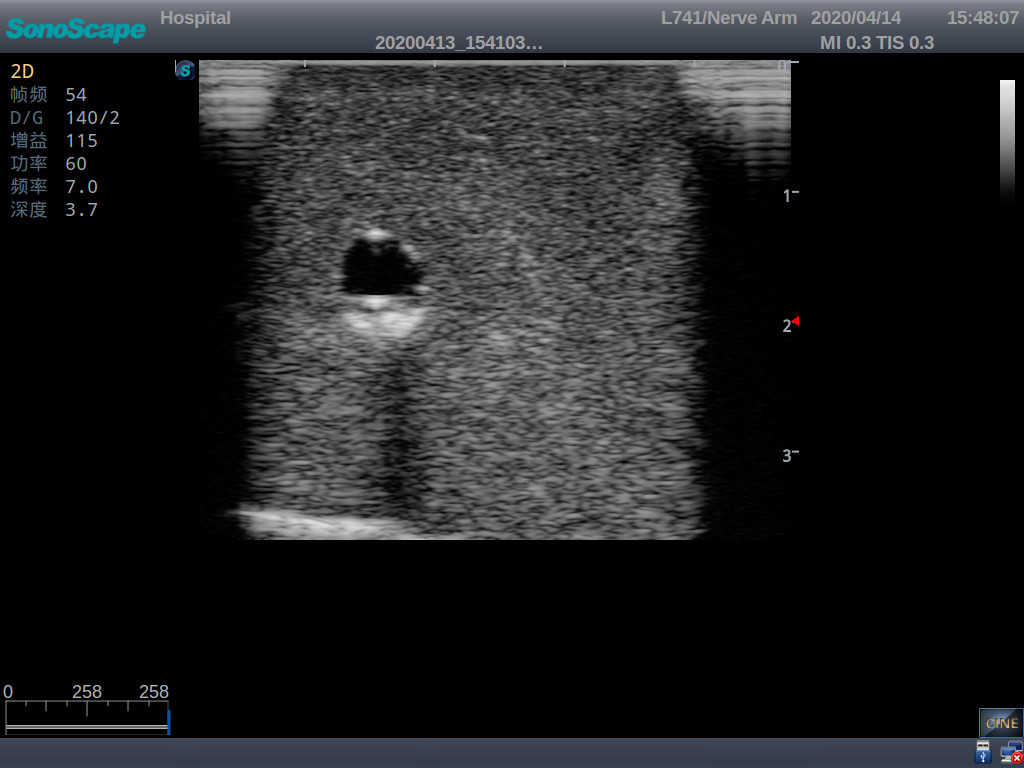

2) It can be used by real ultrasound machines

3) Clear and real images of the tissues and organs (basilic vein and superior vena cava)

4) When conducting vascular puncture, the piercing can be truly felt, and venous blood outflow can be seen